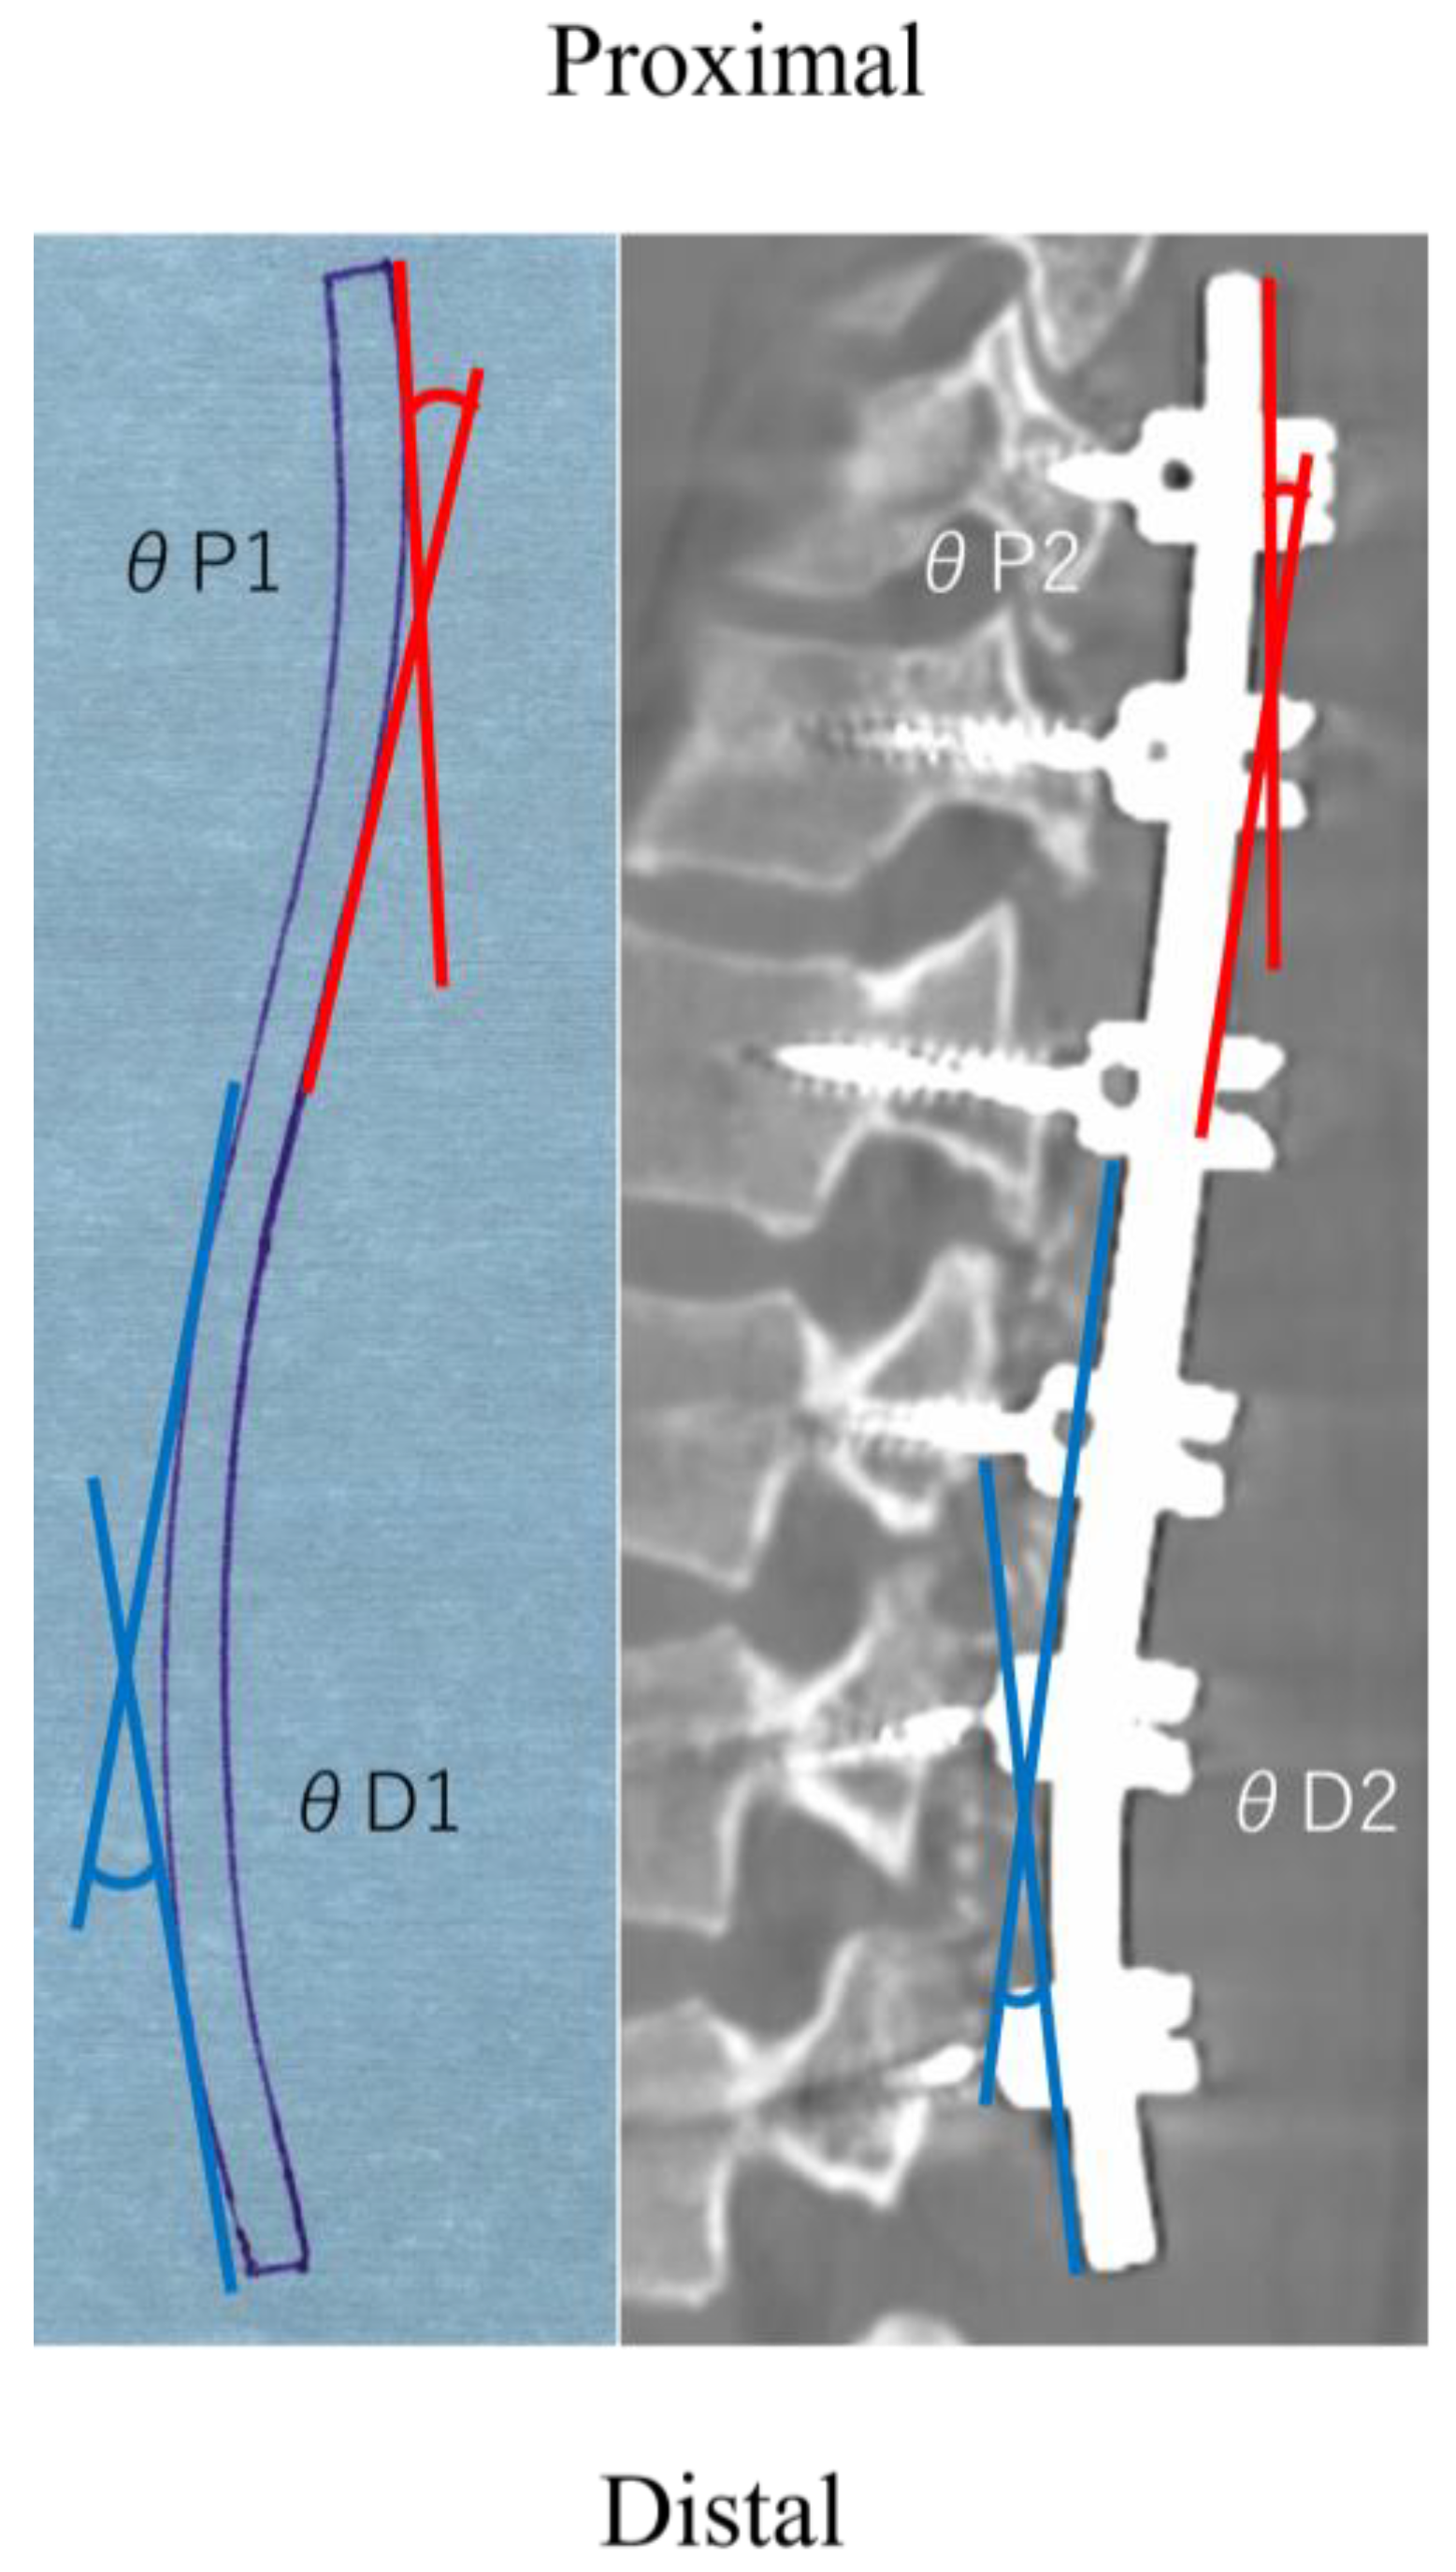

| Proximal rod angle (°) | 18.3 ± 6.7 | 9.3 ± 3.3 | <0.01 |

| Distal rod angle (°) | 30.8 ± 8.0 | 15.9 ± 4.6 | <0.01 |